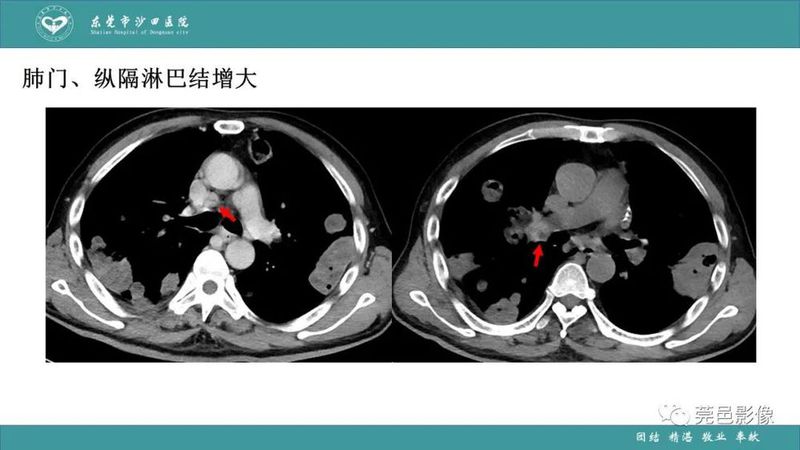

「肺炎克雷伯杆菌肺炎」影像学诊断+鉴别诊断